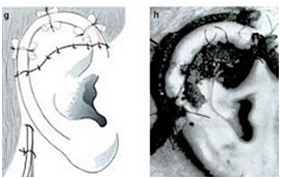

The first stage operation was implantation of the cartilage framework. The skin incised about 3-4 mm lower than the marked height of the stump.7,8 Subcutaneous pocket is developed, about 1 cm larger than the height of the superior helical margin and the post auricular stump skin is sutured to the lower margin of the incision. The framework is attached using 5.0 braided suture and inserted to the pocket. Closure of the skin wound, vacuum drainage, and mattress sutures (Figures 7-10).7

Figure 10 Closure of the skin wound.7